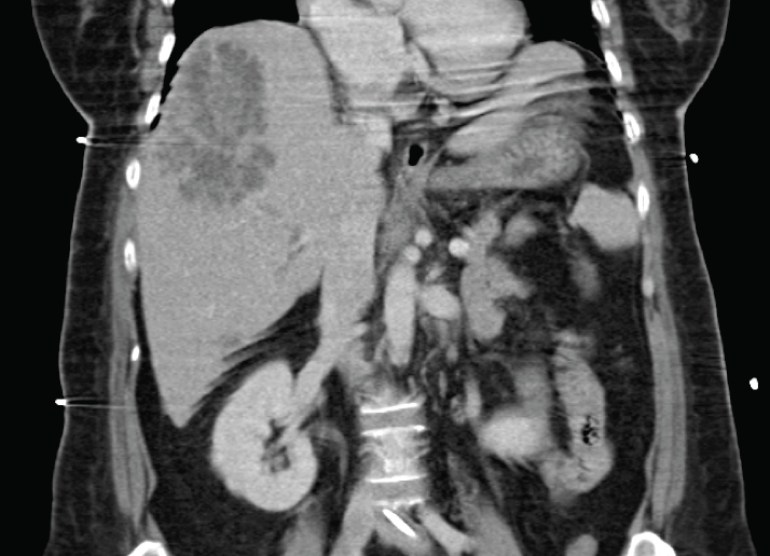

A middle-aged man in his late 50’s presented with fever for 3 days associated with poor appetite and epigastric discomfort. He had been prescribed augmentin by his general practitioner 2 days ago without relief of symptoms. His only premorbid conditions were hypertension and hyperlipidemia, and there was no travel or contact history of significance. Physical examination revealed right hypochondral tenderness, and a CT abdomen was ordered.

In a patient from the community, and in Singapore, this is almost invariably Klebsiella pneumoniae liver abscess. This is the same type of Klebsiella pneumoniae that can cause endophthalmitis as described previously (one can also find some nice pictures and a short microbiological description here).

With the presence of a large liver abscess, drainage is indicated. Years ago, the surgeons from Singapore General Hospital published a “natural history experiment” (surgeons from various surgical teams had different preferences for type of liver abscess drainage) showing that for abscesses that were larger than 5 cm, surgical drainage – as opposed to percutaneous radiologically-guided drainage – resulted in better outcomes in terms of length of stay and number of secondary procedures required. The paper can be read online here. A clinical trial was never performed to validate the results, however, and the lead author of the SGH paper has publicly stated that he felt it would be difficult if not ethically challenging to perform such a trial, because surgical drainage is more invasive and does carry a higher risk compared to percutaneous drainage.